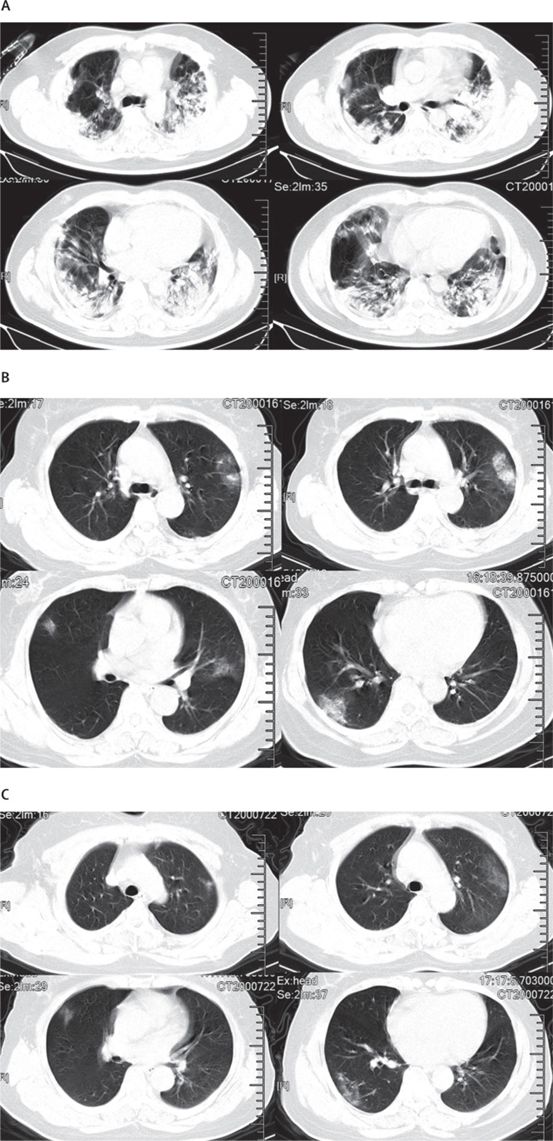

图为肺炎患者的CT显示的不同的症状